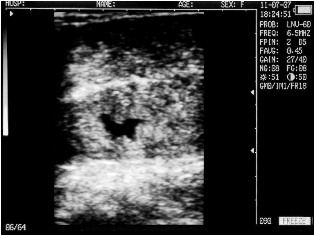

Cow with calf. Deadline - 30 days